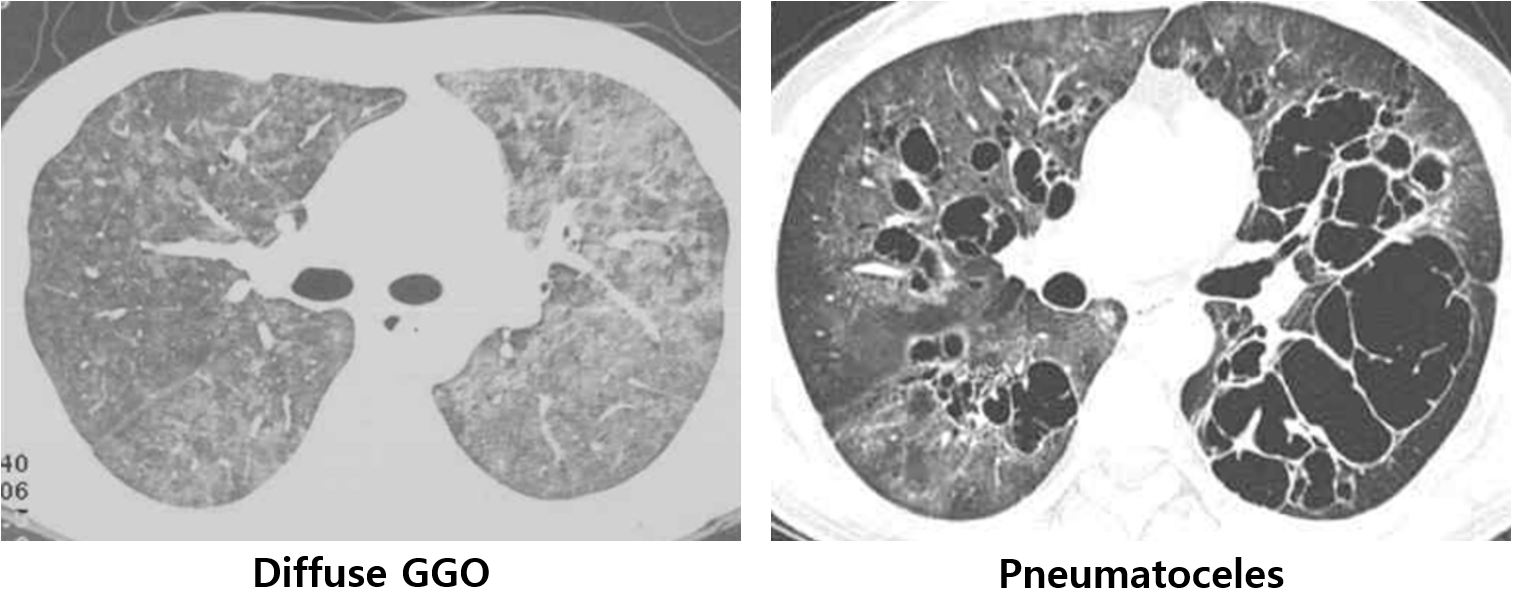

(2) 영상검사: Diffuse GGO → 공기집(pneumatocele) 형성